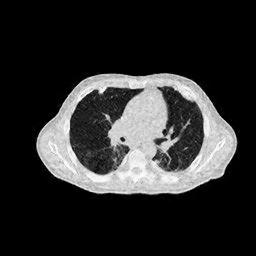

4.5.2 Quantum Noise

To test the proposed method’s performance under the low-dose condition, we repeat the aforementioned reconstruction experiments by using the sinogram data polluted with Poisson-distributed noise. The average number of X-ray photons received by the th detector can be expressed as:

where is the blank measurement (). It is worth mentioning that the sinogram measurements employed in this study are derived from simulations, as opposed to being sourced from an actual instrument. Thus, here is a parameter for relative measurement. Throughout the experiments, is assigned values ranging from to , which correspond to sinogram SNR (dB) values of . It is worth mentioning that analogous experiments were conducted under both few-view and limited-angle scenarios, with the proposed method demonstrating a marked superiority over other methods across all conditions. This enhancement, however, is primarily attributed to the exceptional performance of the proposed method under sparse-measurement circumstances, rather than an increased resistance to noise. To facilitate an equitable comparison, the results displayed in Fig.11 are solely derived from the full-view scenario, which encompasses an angular range of with one view per degree.

(a) ASD-POCS (19.92dB)

(b) RBP-DIP (23.82dB)

(c) DIP (21.88dB)

(d) MED50 (15.61dB)

5 Discussion

In practical applications, the imaged object might exhibit inconsistencies with the training dataset due to various non-ideal factors. The rotation operation in Section 4.5 serves as a simplified simulation of such discrepancies, which may arise from differing poses of patients. The impact on reconstruction accuracy is shown in Fig.9. The comparison between Fig.5b and Fig.9 reveals that the pre-trained MED50 method is predominantly affected by a considerable decline in SNR. The reconstruction results are also presented in Fig.10. In contrast to the first row of Fig.7, the MED50 reconstruction result lacks a completely black background and exhibits horizontal artifacts in the non-empty region. This observation suggests that MED50 cannot effectively handle the perturbations in the inference data.

Additionally, experiments were conducted under low-dose conditions, as demonstrated in Fig.11. MED50 was found to be the most vulnerable to sinogram noise, while RED-CNN exhibited relative insensitivity to perturbations due to its patch-based learning approach.

The proposed RBP-DIP framework does not necessitate any training images and attains the highest reconstruction accuracy in both experiments. Moreover, additional constraints or regularizations can be directly incorporated into the objective function or indirectly integrated into the RBP connection, enabling enhanced handling of various factors without retraining.